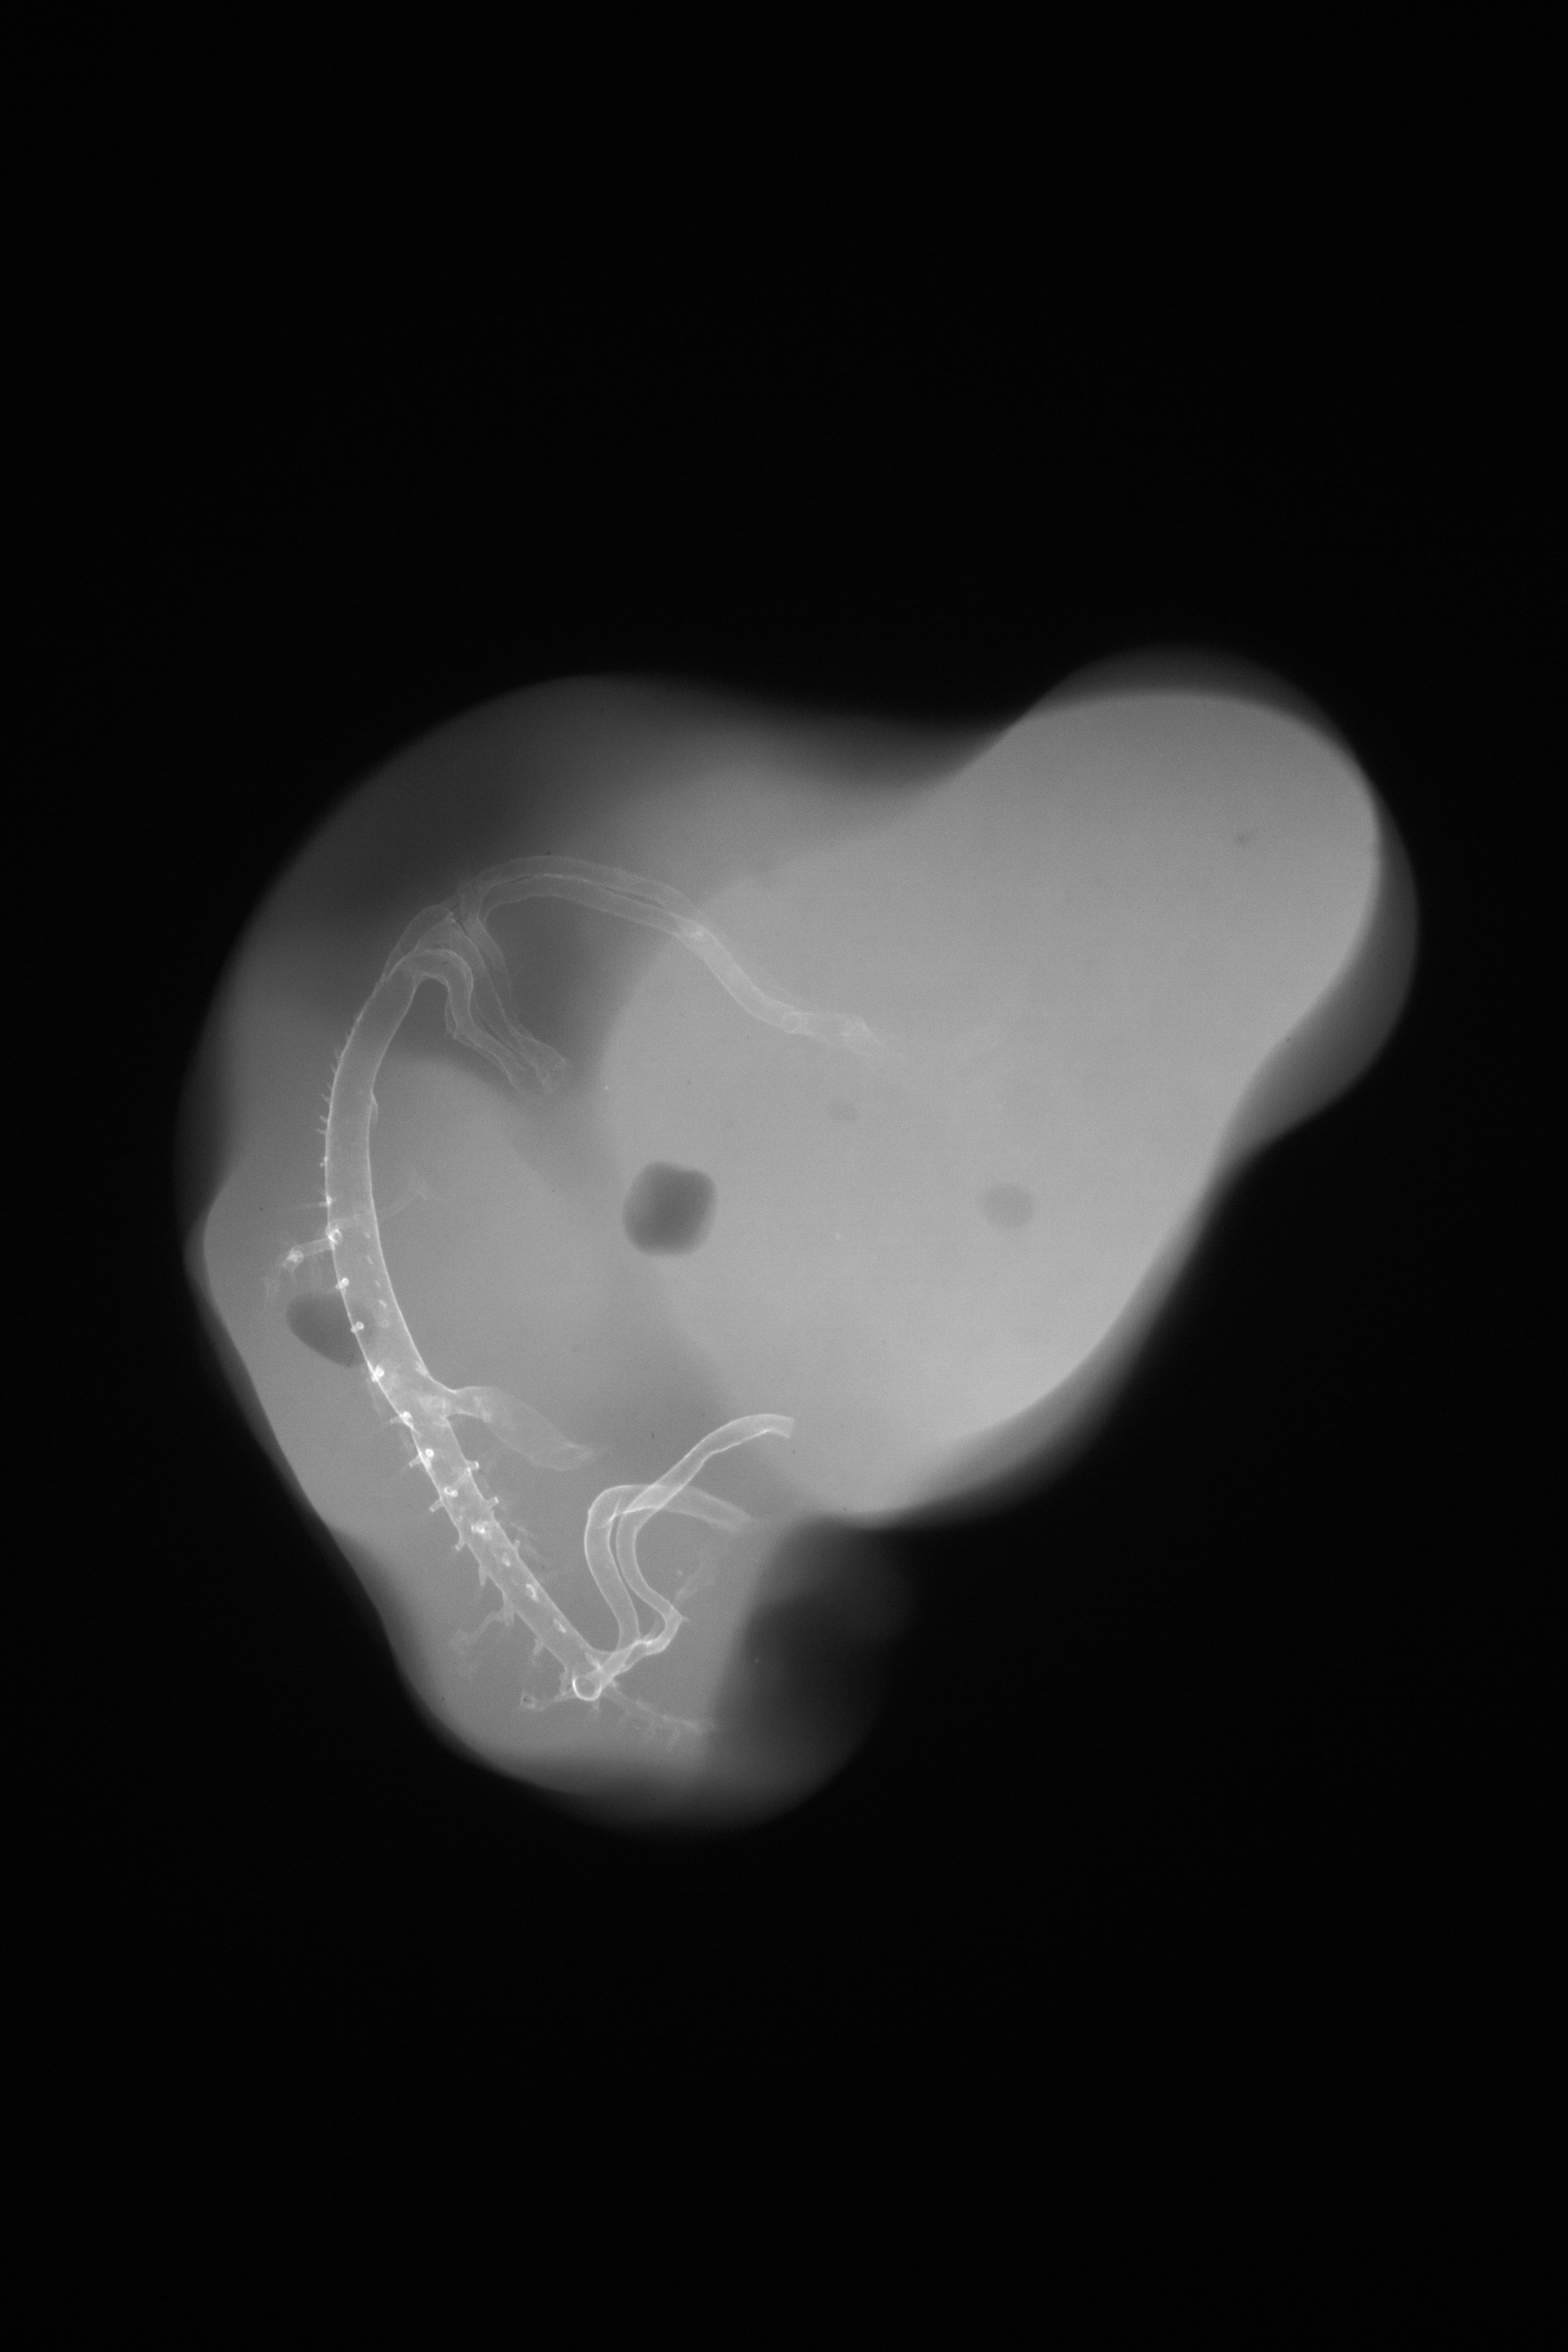

Chick Embryo Microangiography

Hamburger-Hamilton (HH) Stage 27 (approx. 5 - 5.5 days)

X-Ray Micrographs